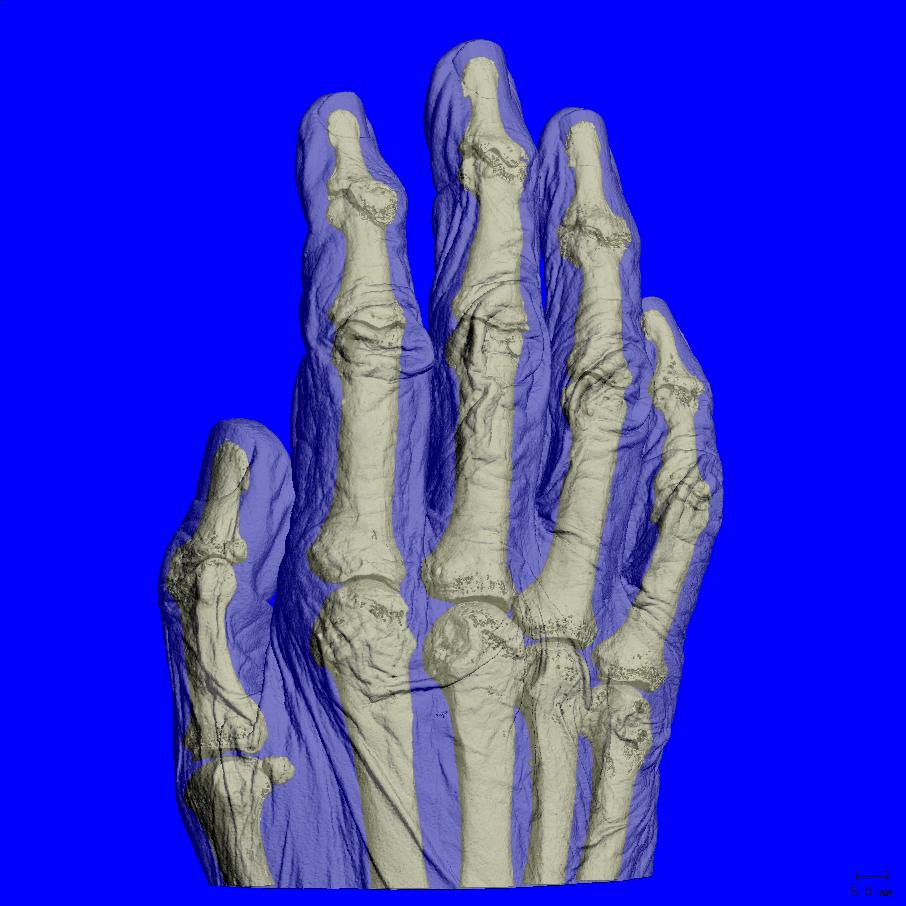

| 最大扫描尺寸 | 140 x 225 mm (ØxL) |

| 最大试样尺寸 | 170 mm * (Ø) * * |